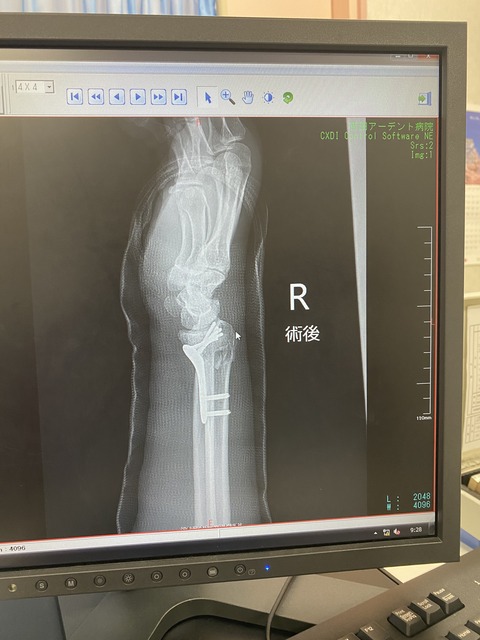

最後におかんの採血なんやけど、右腕はギブスであかんし